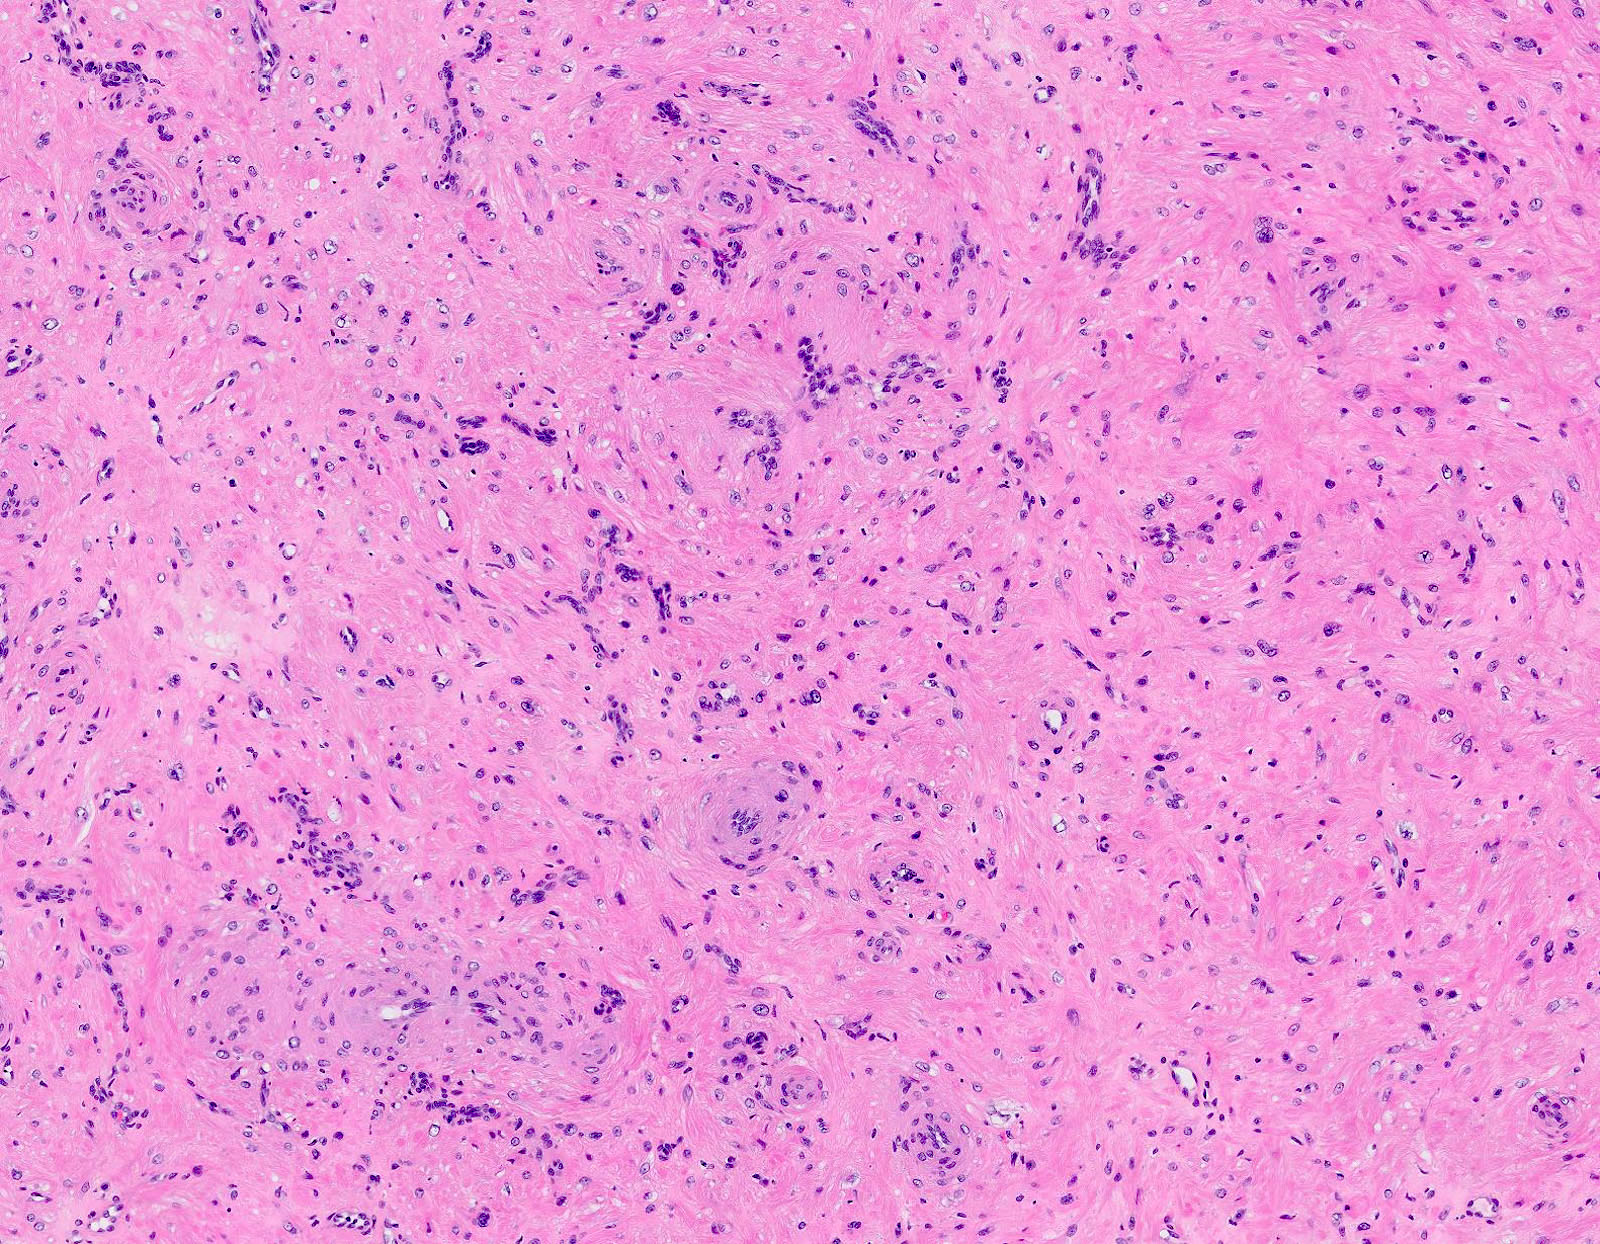

Microscopic (histologic) description

- Encapsulated proliferation of eosinophilic smooth muscle cells with minimal nuclear pleomorphism

- Rounded or slit-like veins with muscular walls present within the tumor (J Cutan Pathol 2017;44:342)

- Tumors can further be classified into 3 subcategories, first described by Morimoto et al:

- Solid type: smooth muscle bundles surround numerous small slit-like channels

- Cavernous type: dilated vascular channels, the walls of which are difficult to distinguish from the intervascular smooth muscle

- Venous type: thick walled vessels that are easily distinguished from the intervascular smooth muscle

- Calcification and marked degeneration, including hyalinization and myxoid changes, may be present (J Cutan Pathol 2017;44:342, J Ultrasound Med 2019;38:1201)

Microscopic (histologic) images

Contributed by Ohoud Aljarbou, M.D., Jijgee Munkhdelger, M.D., Ph.D. and Andrey Bychkov, M.D., Ph.D.

A. Angioleiomyoma. A mixture of smooth muscle bundles arranged in small fascicles and intervening vascular channels is noted. The concentric perivascular spindle cell proliferation which is characteristic for myopericytoma is absent. There are no glomus cells seen. Adipocytes are not seen in this image, which makes angiomyolipoma less likely.